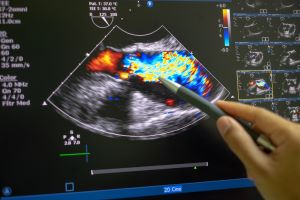

La ecocardiografía se ha instaurado como una herramienta clave para la evaluación hemodinámica de los pacientes críticos. Al ser una herramienta no invasiva, reproducible y al lado de la cama del paciente, permite realizar una evaluación global del estado funcional hemodinámico de los pacientes. Sin embargo, para poder ser una herramienta efectiva y confiable, el aprendizaje del uso de la ultrasonografía debe ser realizado bajo un contexto estructurado y basado en protocolos de evaluación clínica.

El aprendizaje de la ecocardiografía es clave para brindar una atención integral a pacientes en cuidados intensivos, incluso, se ha propuesto como un estándar de cuidado por algunas sociedades científicas a nivel internacional.

El objetivo de este curso es contribuir a formar profesionales de cuidados intensivos con las competencias básicas para el uso de la ecocardiografía en la atención de un paciente crítico adulto.